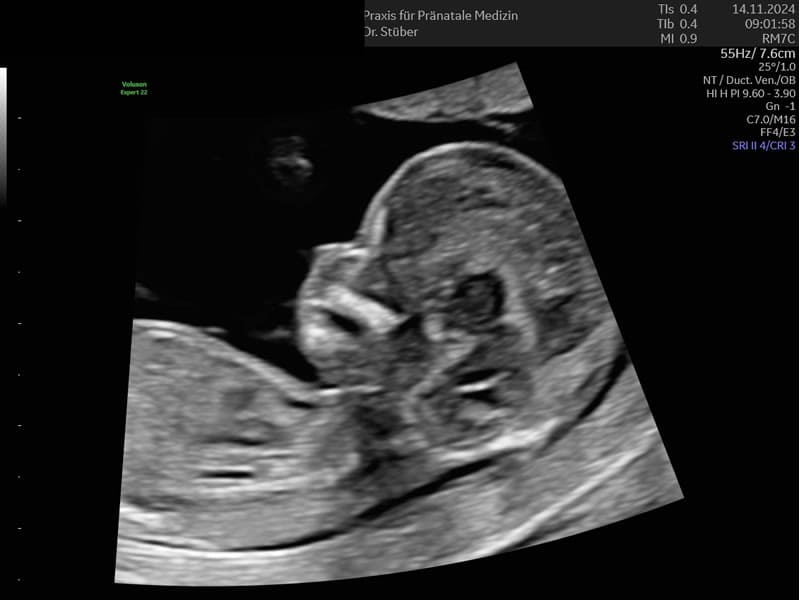

Im ersten Trimenon (1. Schwangerschaftsdrittel) bieten wir Ihnen verschiedene Untersuchungen an. Ab der 12. SSW können unter anderem bereits Kopf, Herz und Extremitäten untersucht und einige Fehlbildungen ausgeschlossen werden.

Im Ersttrimesterscreening (12-14 SSW) können wir durch Messen der Nackentransparenz, Darstellung des Nasenbeins und weitere Parameter zusätzlich das Risiko für Chromosomenstörungen bei Ihrem Kind ermitteln.

Ultraschall Ersttrimester Screening